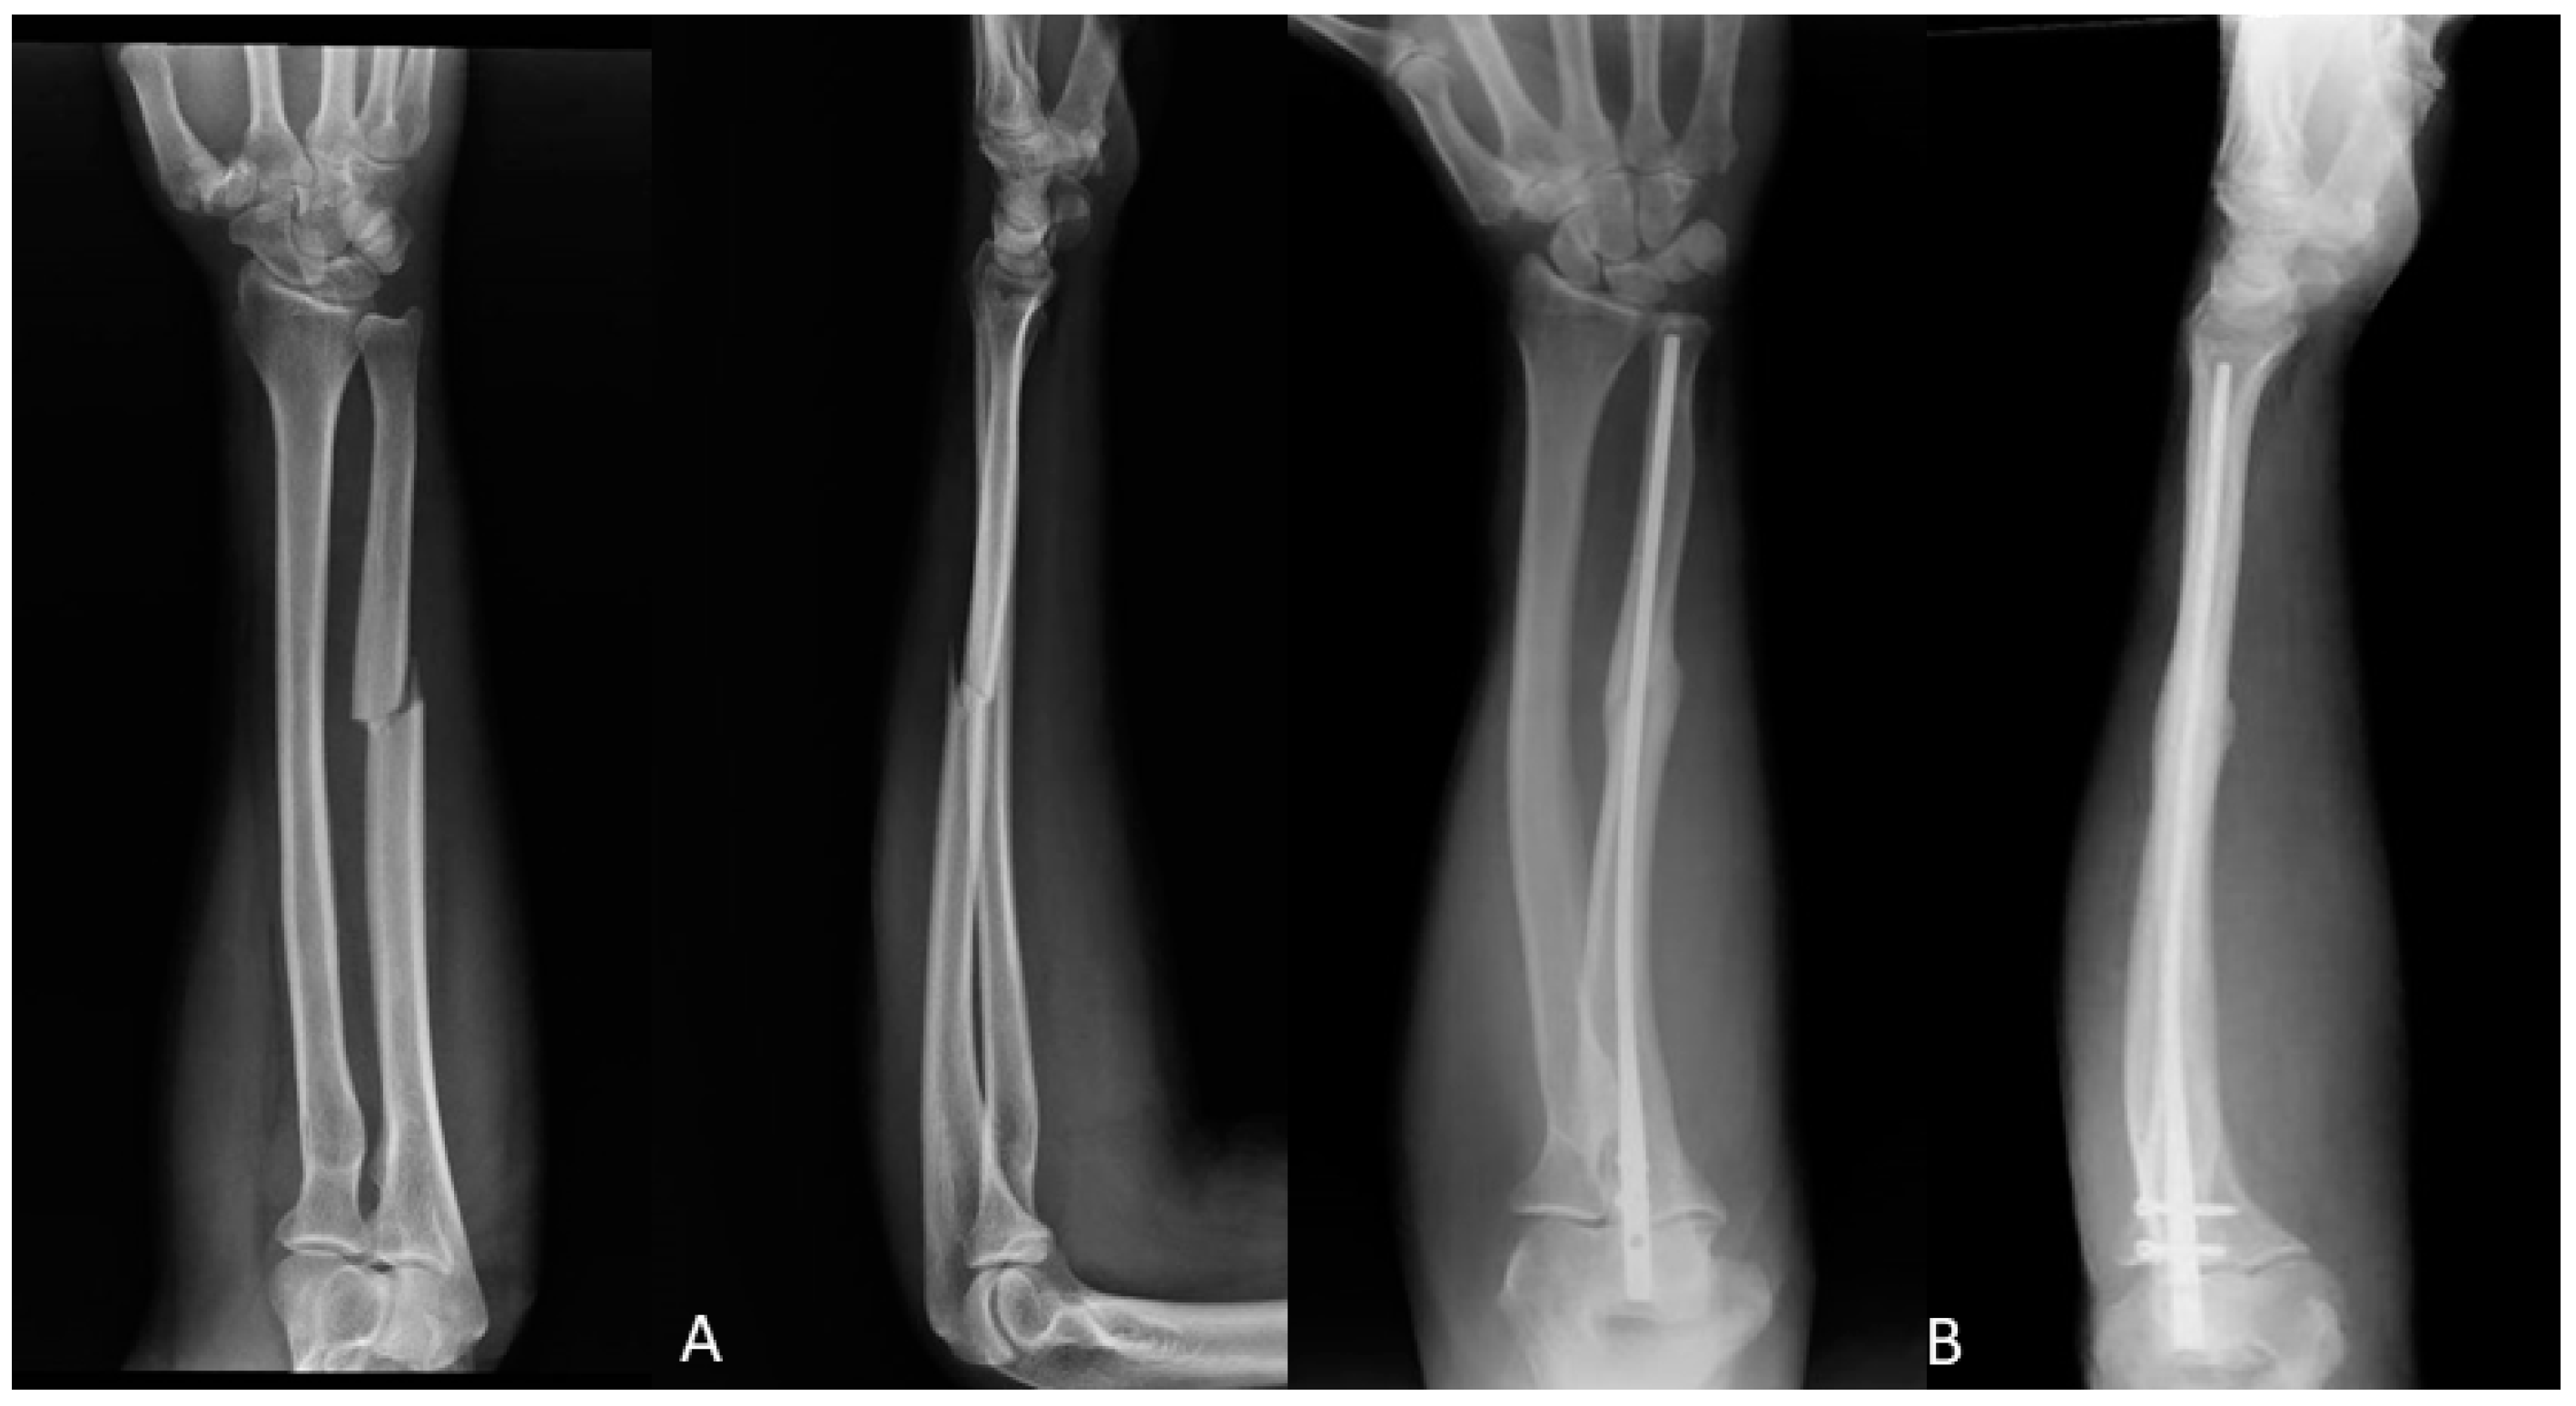

2.2. Surgical Techniques

2.2.2. Intramedullary Nail (IMN)